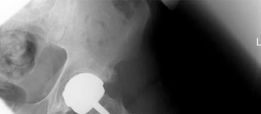

The patient was transferred to the Post-Anesthesia Care Unit in stable condition. Postoperative radiographs confirmed excellent component positioning, with the femoral component in slight valgus relative to the femoral neck, no evidence of notching, and the acetabular component seated with appropriate inclination and anteversion.

Image